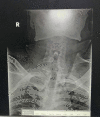

Cervical spine assessment is an important step in patients who sustained trauma. Klippel-Feil syndrome (KFS) is a complex syndrome with an abnormal fusion of cervical vertebrae at C2 and C3, which is caused by a failure in the division or normal segmentation of the cervical spine vertebrae in early fetal development. This condition leads to a characteristic appearance of a short neck, low hairline, facial asymmetry, and limited neck mobility. People with congenital defects like KFS are more prone to cervical spine injury. KFS is a relatively rare disease. Trivial trauma can lead to neurologic symptoms in such individuals. We present a 32-year-old male, with an alleged history of falls from height with traumatic injury to his head and spine. Following the event, he was unable to move all four limbs. The patient's short neck was noted. Magnetic resonance imaging (MRI) of the spine revealed multilevel fusion of four cervical vertebrae (C3-C7) with a single fused spine which is highly uncommon. Myelopathy secondary to C3-C4 disk protrusion is also seen. The patient was diagnosed with KFS and managed conservatively. The abnormal fusion in KFS predisposes to neurologic injury owing to altered biomechanics of the spine leading to hypermobility of the adjacent normal spine, spondylolisthesis, and stenosis, thereby increasing the likelihood of injuries. Screening and identification of KFS in young children are essential as counseling for lesser strenuous activity might avoid neurological injury and promote better neurological outcomes in the future.